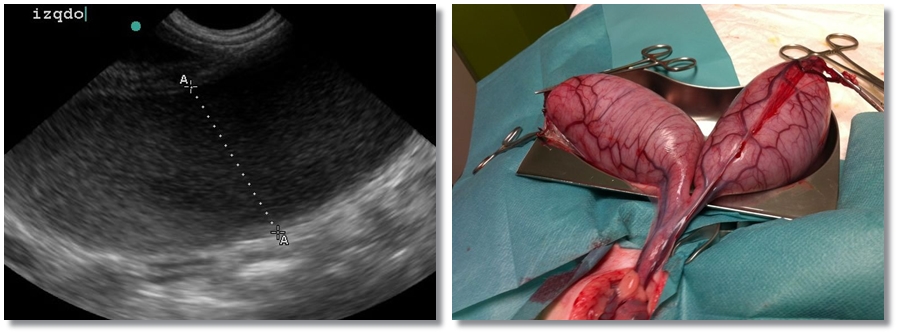

Tumor Explénico / Tumor de Bazo

Paciente con distensión abdominal junto con apatía que presenta ligera anemia en analítica. Se realiza…